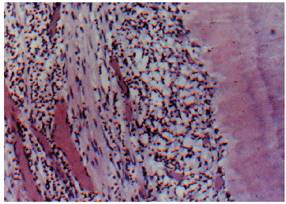

Pulpal Repair

Reparative or irregular dentin is deposited to form a protective barrier for

the pulp tissue and is generally localized to the injury site. This abnormal

dentin forms in response to intense and aggressive pulpal irritants that have

reached the limit of pulp tolerance (eg, erosion, abrasion, caries, dentinal

exposure by fracture, decay or mechanical tooth reduction, traumatic injury,

caustic medicaments, and harmful filling materials).

The histologic appearance of reparative dentin (Figure 19-30) demonstrates dentinal tubules that

are irregular, tortuous, or even absent. The increased thickness of the total

dentin is likely the reason for patients having decreased responses to cold

stimuli as time passes following a dental procedure. Quantitatively, it is

noted that the greater the degree of the "insult" caused by

preparations and restorative materials, the greater the amount of reparative

dentin that forms.

Although this calcified solid wall is considered beneficial and capable of

resisting further episodes of irritation, this healing phenomenon decreases the

ability of the tooth to respond to pulp testing at a later date.

Figure 19-30: Reparative dentin is deposited at specific sites as a result of injury (ie, caries, restorative procedures, attrition, or trauma).